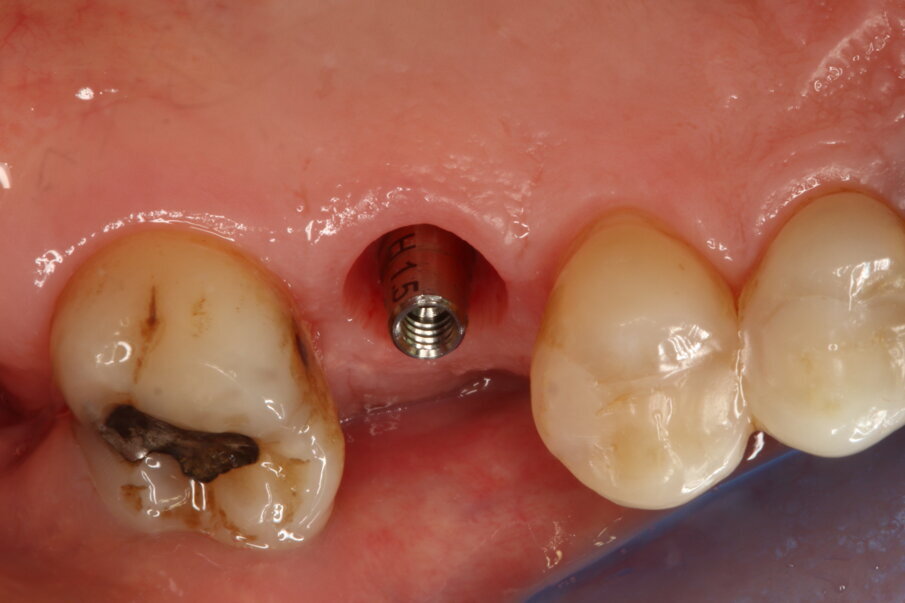

Posizionamento implantare

È stato inserito un impianto tronco-conico di 10 mm di lunghezza e 4,2 mm di diametro (AoN SLC con connessione Revcon) con torque di inserzione di 35 N e valori di ISQ pari a 66 in direzione vestibolo-linguale e 68 in direzione mesio-distale20. È stato applicato un moncone conometrico dritto e avvitato a 35 N con relativa cappa di guarigione in peek21 (Figg. 4, 5).

Fig. 4_Inserimento dell’impianto (AoN SLC con connessione Revcon).